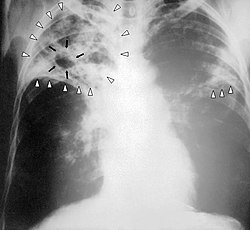

Ağciyərlərin vərəmi uzunmüddətli öskürək, subfebril(bəzən daha çox) temperatur, bəlğəm, bəzən qan hayxırma, döş qəfəsində ağrı və s. əlamətlərlə gedir. Bundan başqa əsəbilik, gecə tərləmələri, arıqlama, arterial təzyiqin enməsi, böyrəküstü vəzlərin fəaliyyətinin zəifləməsı kimi ümumi simptomlar xəstəni narahat edir. Miliar vərəmdə proses kəskin olub yüksək temperaturla gedir və bu zaman oskürək, bəlğəm kimi əlamətlər olmaya da bilər, intoksikasiya əlamətləri, tifəbənzər əlamətlər üstünlük təşkil edir. Vərəmin gec, ağırlaşmiş mərhələlərində ürək, qan-damar sistemi, tənəffüs çatışmazlığı əlamətləri meydana çıxır. Xəstənin nəbzi tezləşır(taxikardiya), təngnəfəslik, periferik sianoz(dodaqların, barmaqların göyərməsi), tənəffüs prosesinə köməkçi əzələlərin qoşulması kimil əlamətlər əmələ gəlir. Ağciyər vərəminin bəzi formaları əlamətsiz keçə bilər(ocaqlı vərəm, tuberkulema). Diaqnoz: Vərəmin diaqnozunu qoymaq üçün minimal 3 diaqnostik üsul tətbiq olunur: Ağciyərlərin rentgenoqramması(və ya flüoroqrafiya), Mantu sınağı, Bəlğəmin mikroskopik müayinəsi. Bundan sonra lazım gələrsə əlavə diaqnostik üsullar da tətbiq oluna bilər. Qanın ümumi analizində EÇS artır, eozonofillərin artması(eozonofiliya), limfositlərin azalması (limfopeniya) aşkar edilir. Uşaqlarda və yeniyetmələrdə ilk dəfə Mantu sınağı "+" nəticə verirsə bu "viraj" adlanır və ilkin yoluxmanı göstərir. Yoluxmadan 2 ay sonra viraj aşkar oluna bilər. Müalicəsi: Vərəm sağalan xəstəlikdir. Yalnız gecikmiə mərhələlərdə bu mümkün olmaya bilər. Vərəmin müalicəsi uzun çəkir. Qanuna əsasən Azərbaycan Respublikasında vərəmin müalicəsi pulsuzdur. Pəhriz təyin edilir. Belə ki, xəstə yaxşı qidalanmalı, gün ərzində bütün lazım olan qida maddələrini və kalorini qəbul etməlidir. Qidada zülallar, vitaminlər, mineral maddələr, yağlar miqdarında gündəlik tələbatı ödəməlidir. Ağartılar, yumurta, balıq əti, meyvə-tərəvəz və s. qida növləri yeməkdə üstünlük təşkil etməlidir. Konservativ müalicəyə kimyəvi preparatlar, lazım gələrsə hormonal, desensibilizə edici preparatlar, vitaminlər, sanator-kurort müalicəsi, pəhriz daxildir. Konservativ müalicə nəticə verməzsə cərrahi müalicə aparıla bilər.[mənbə göstərilməlidir]